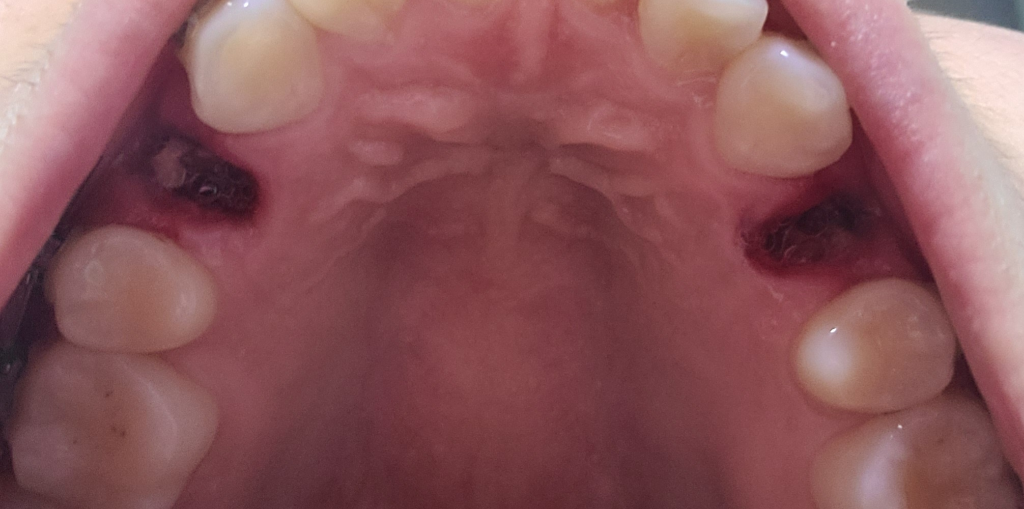

오늘 교정 목적으로 상악 소구치 2개를 발치하였습니다. 거즈로 약 2시간 반정도 지혈하고 피가 멎어 죽을 먹고 약도 먹었습니다. 근데 한쪽에 흰색의 무언가가 보여서 죽인줄알고 양치 후 물가글을 했는데도 빠지지않아서요.

• 1번 째 사진

사진상으로는 드라이소켓이나 음식물이 낀 양상은 아니고 잇몸 치유 과정에 나오는 육아조직으로 보여집니다

거즈 잘 물고 있다가 피가 멎었을 때 거즈를 뺐고, 기타 주의사항도 잘 지키셨다면 드라이소켓이나 기타 감염의 가능성은 크지 않습니다

그냥두면 저절로 없어집니다. 흰색의 딱지 앉은 것으로 보면 됩니다. 하얀 잇몸막으로 시간 지나면 저절로 떨어져 없어집니다.